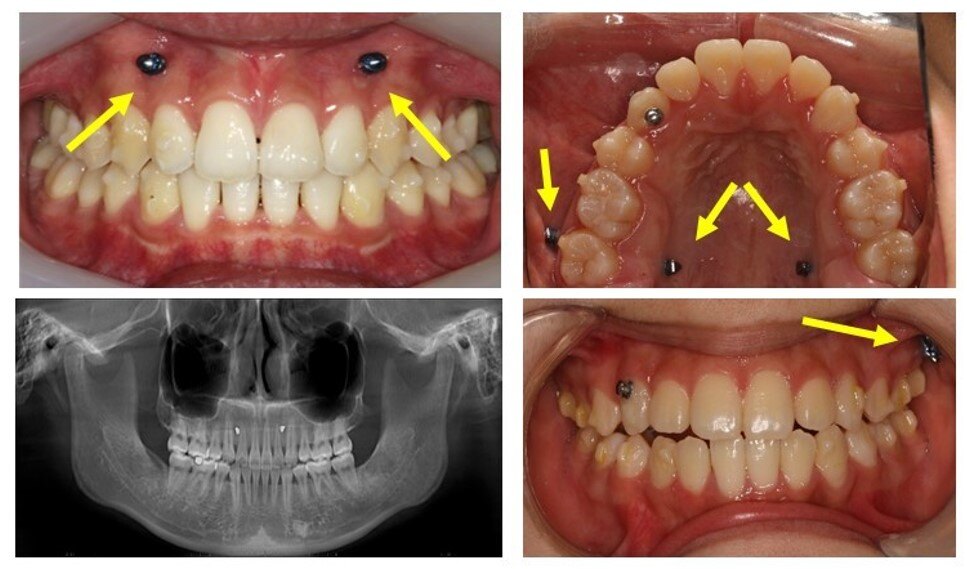

正畸骨钉(支抗钉)

正畸支抗钉,又叫骨钉,是由生物相容性高的.